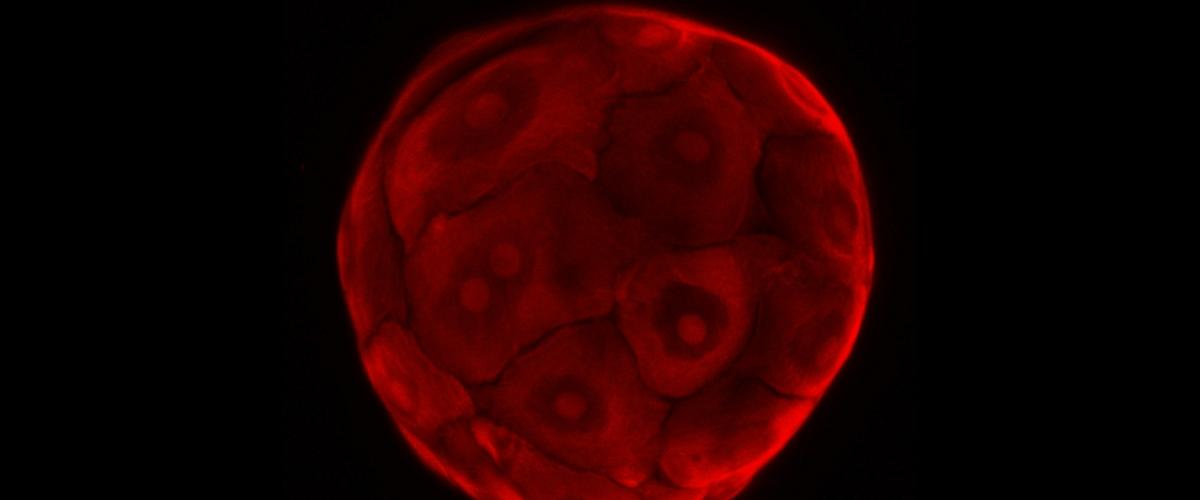

Оказалось, что продуцируемый геном белок MLLT3 обеспечивает столовые клетки «инструкциями» для поддержания способности к самообновлению. В этом механизме также участвуют и другие регуляторные белки, чтобы клетки имели возможность делиться. Лабораторные эксперименты показали, что активность гена MLLT3 в стволовых клетках заставила их активно размножаться в чашке Петри.

Важно, что скорость самообновления клеток была безопасной. Это значит, что клетки можно использовать в дальнейшем. Для начала их подсадили мышам, и они хорошо интегрировались в организмах грызунов, продуцируя все типы клеток крови.